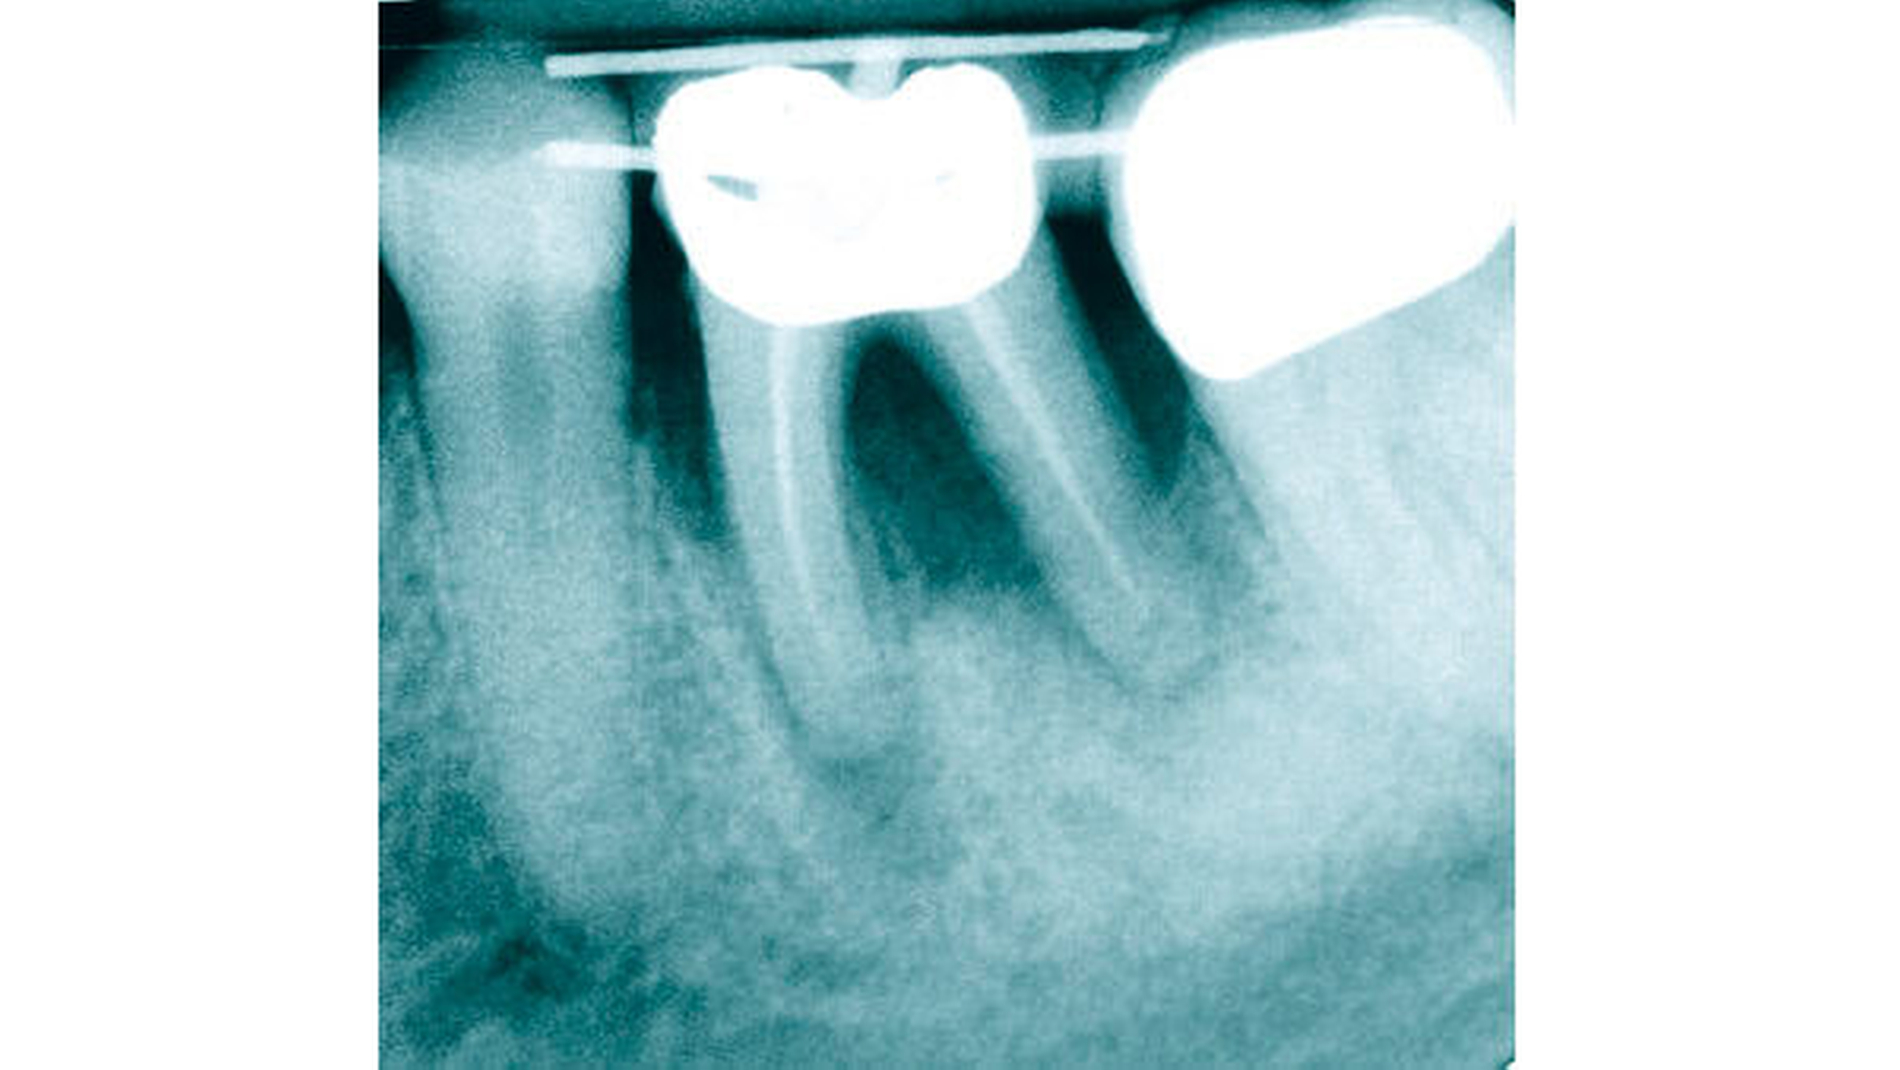

Bei Zahn 36 zeigte sich zu Beginn der Behandlung eine massive Osteolyse (Abbildung 8). Die anfängliche Diagnose lautete: massiv vorangeschrittene Paro-Endo-Läsion mit Osteolyse von rund 80 Prozent mit Furkations- und Lockerungsgrad von jeweils III und mit Pusaustritt aus einer vestibulären Fistel. Daher war die Prognose: nicht erhaltungswürdiger Zahn.

Um eine spätere, aufwendige Augmentation zu vermeiden und über einen längeren Zeitraum knochenregenerativ wirken zu können, sollte Zahn 36 vor der späteren Extraktion forciert aus der Alveole bewegt werden. Die insuffiziente Wurzelbehandlung spielte zu diesem Zeitpunkt aufgrund der infausten Prognose keine Rolle.

Nach forcierter Extrusion (Abbildung 9) mit vier Gummiwechseln innerhalb von acht Tagen und einer ersten Stabilisierungsphase zeigten sich im Röntgenbild (Abbildung 10) erste, deutliche Reossifkationen.